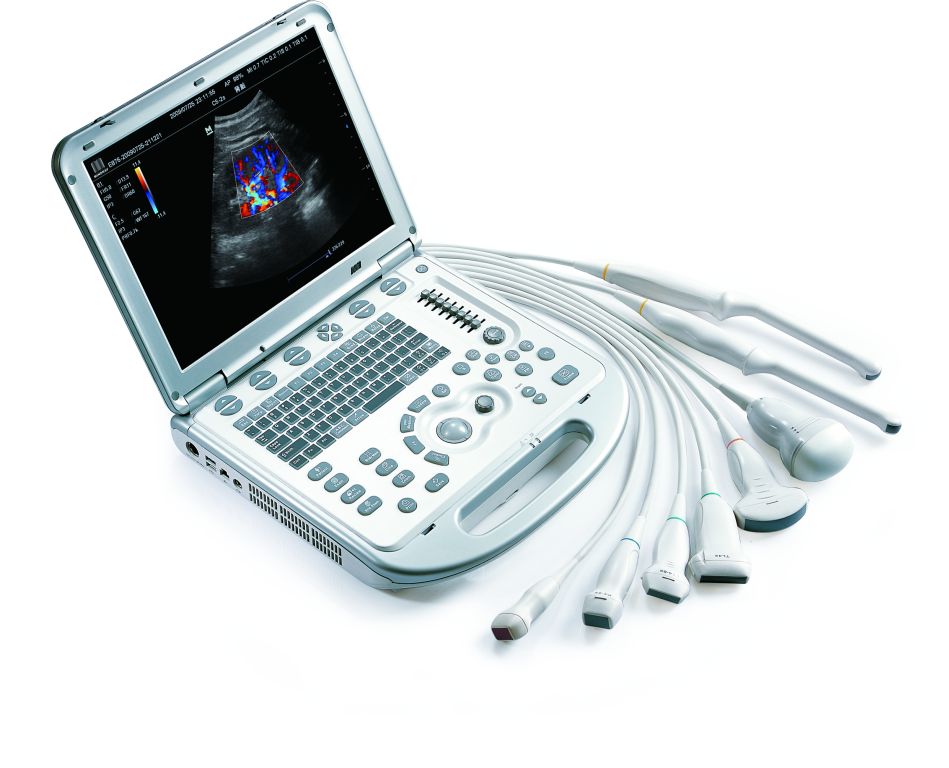

- High density sondy

- široká ponuka multifrekvenčných sond

- možnosť pripojenia špeciálnych sond, ako napr.3 druhy phased array sondy, TEE sonda, Pedoff sonda, lineárna rektálna sonda, vysokofrekvenčná HD lineárna sonda, 4D konvexná sonda...

- 6 frekvencií na každej sonde, z toho dve sú harmonické

- 1 konektor na pripojenie UZV sond (rozšíriteľné na 3)